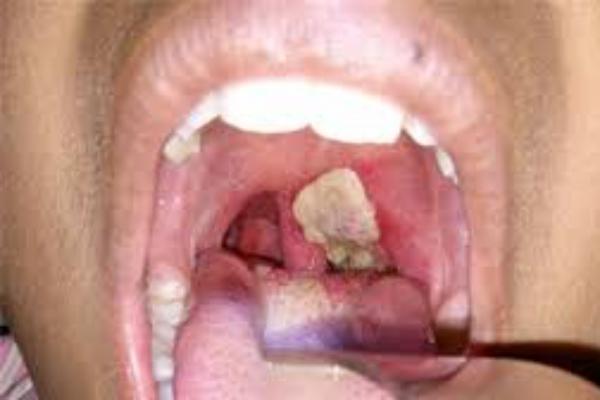

Ngày 3/7, Bệnh viện nhi Gia Lai tiếp nhận bệnh nhân Vung trong tình trạng sốt, ho, đau họng. Theo kết quả xét nghiệm, cháu Vung bị bệnh bạch hầu.